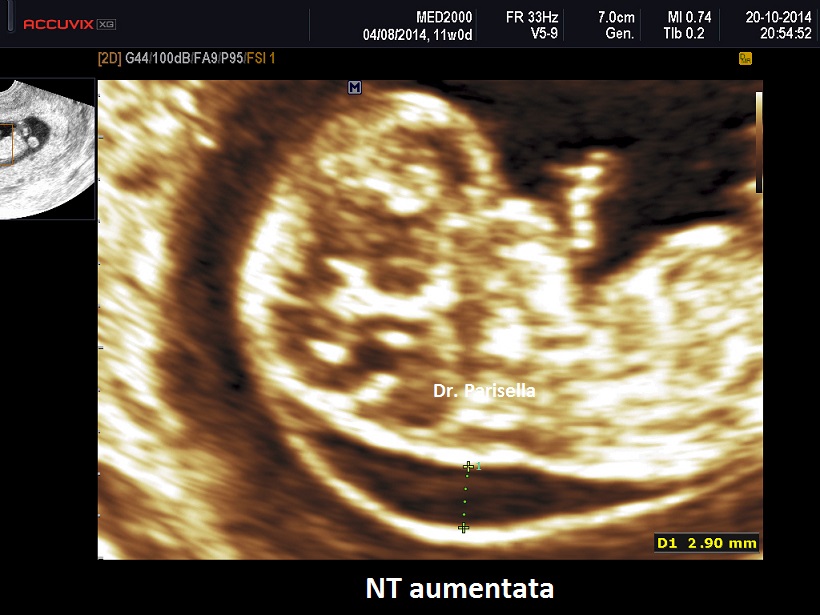

La translucenza nucale è un marker rilevabile tra le 11 settimane + 0 gg. e 13 settimane + 6 gg. di gestazione, più precisamente in un range del CRL compreso tra 45 mm. e 84 mm. Essa appare caratterizzata ecograficamente dall'accumulo sottocutaneo di fluido dietro il collo fetale nel primo trimestre di gravidanza. La Fetal Medicine Foundation (FMF) di Londra ha dettato i criteri da adottare per una corretta misurazione della NT:

- posizionamento dei calipers "on to on": i cursori devono essere posizionati sui bordi interni delle linee che delimitano lo spazio della translucenza nucale senza che le linee orizzontali dei cursori protudano in questo spazio (vedasi immagine)

- la misurazione deve essere eseguita in corrispondenza della parte più ampia della Translucenza

Si è osservato che nei feti sani lo spessore della NT tende ad aumentare con l'incremento del CRL; di conseguenza anche i valori soglia della NT cambiano col variare dei valori del CRL: a 11 settimane con un CRL di 45 mm. i valori possono variare da 1,2 mm. (50° percentile) a 2,1 mm. (95° percentile), mentre a 13 sett. + 6 gg. con un CRL di 84 mm., i valori possono variare da 1,9 mm. (50° percentile) a 2,7 mm. (95° percentile); il 99° percentile non varia col CRL ed è circa 3,5 mm. Si intende per translucenza nucale aumentata uno spessore di NT al disopra del 95° percentile. Con un software dedicato che prende in considerazione NT, CRL, età materna e Frequenza Cardiaca Fetale (FHR), con un cut-off attualmente di 1/100 (Fetal Medicine Foundation) è possibile calcolare il rischio di anomalie cromosomiche con una sensibilità di circa il 90% ed una percentuale di falsi positivi di circa il 5%. La FHR assume notevole importanza nello screening della Trisomia 13: infatti circa l'85% dei feti con Trisomia 13 hanno una frequenza cardiaca al disopra del 95° percentile; nella Trisomia 21 solo il 15% dei feti ha un lieve aumento della FHR oltre il 95° percentile, mentre nella Trisomia 18 solo il 15% dei feti ha una lieve diminuzione della FHR al disotto del 5° percentile.

Nei feti in cui vi è una NT aumentata e cariotipo normale viene riportata una maggiore frequenza di cardiopatie congenite, displasie scheletriche, sindromi genetiche, anomalie strutturali.

Le principali anomalie congenite associate alla NT aumentata e cariotipo normale sono le cardiopatie congenite.